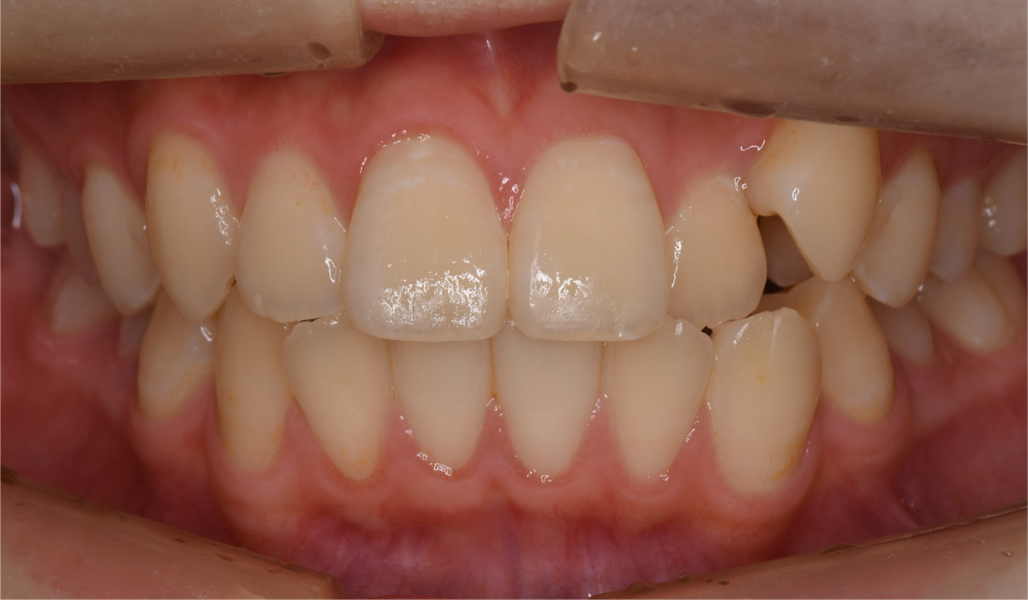

マウスピース型矯正装置(インビザライン)の症例

マウスピース型矯正装置(インビザライン)を使用した歯列矯正